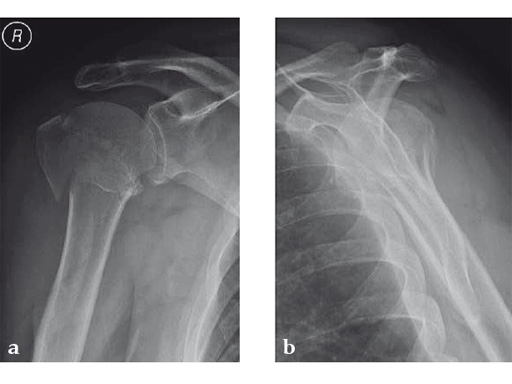

Case 3: Three-part varus displaced fracture with head-split component in a 60-year-old woman.

This case is an illustration of the application of the new nail in a borderline indication. Head-split fractures remain a challenge whatever implant is used for fixation.